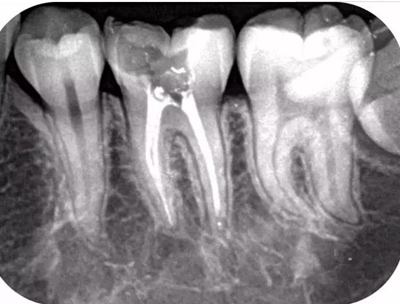

而本寶的拍照水平真是沒SEI了,高清X光影像,分辨率達(dá)12LP/MM,所有牙齒baby在我面前都是赤裸裸的,清晰到毫米以內(nèi)的異常都能捕捉得到。

(本寶拍的牙片,夠不夠赤果果)